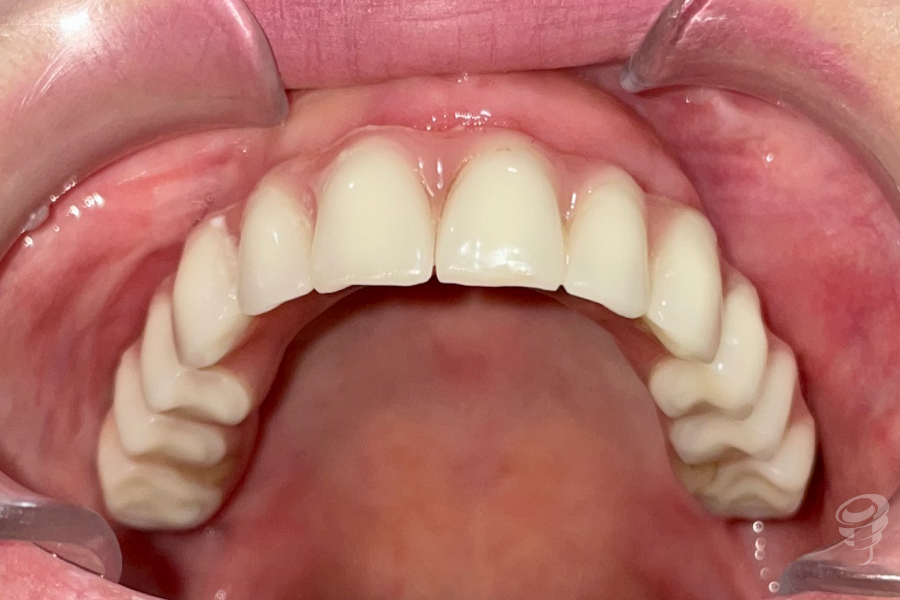

Imagen 14 – Estado inicial